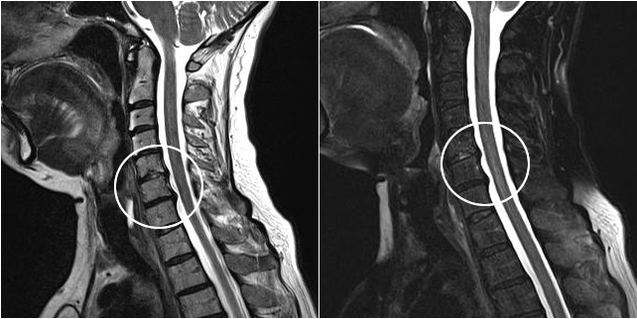

Os métodos de diagnóstico modernos inclúen a resonancia magnética e a TC, que permiten estudar con maior precisión os procesos de destrución da cartilaxe e do tecido óseo. Esta técnica tamén se pode usar para diagnosticar convenientemente hernias e outros defectos dos tecidos brandos preto da orixe da enfermidade.